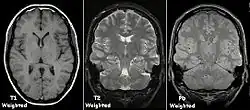

Magnetic resonance imaging (MRI) is a common form of biological data visualization used to form pictures of internal biological processes. Different settings of radiofrequency pulses and gradients result in different image appearances; these combinations are known as MRI sequences. A particularly notable subset of MRI is magnetic resonance angiography, which is a group of techniques used to image arteries and veins. MRI's imaging utility is further expanded upon by diffusion MRI and functional MRI, which can be used to capture neuronal tracts and blood flow respectively.

Diffusion MRI further relies on diffusion tensor imaging (DTI), which measures water molecule diffusion and directionality, and diffusion basis spectrum imaging (DBSI), which extracts multiple anisotropic and isotropic diffusion tensors.[39][40] Functional MRI relies on blood-oxygen-level dependent (BOLD) contrast, which measures the proportion of oxygenated hemoglobin in specific areas of the brain; this allows it to measure and model brain activity based on blood flow.[41] Further MRI techniques include saturation pulses (used to reduce motion artifacts), gradient echo (such as dynamic contrast enhancement), spin echo, and diffusion weighting (a signal contrast generation method based on differences in Brownian motion).[42][43][44]

In general, two aspects of the relaxation process are measured: the time taken for the magnetic vector to return to its resting state (also known as T1 or spin–lattice relaxation), and the time taken for the axial spin of the hydrogen protons to return to its resting state (also known as T2 or spin–spin relaxation).[47] To create a T1-weighted image, the MR signal is measured by changing the amount of time between RF pulses (also known as the time to repeat, or TR). To create a T2-weighted image, the MR signal is measured by changing the amount of time between delivering the RF pulse and receiving the RF energy signals from the hydrogen protons (also known as the time to echo, or TE). The dominant signal intensities of T1 image weighting are fluid (black due to low intensity), muscle (grey due to intermediate signal intensity), and fat (white due to high signal intensity). Fat suppression is applied to many T1 weighted sequences to suppress the brightness of the signal created by it. The dominant signal intensities of T2 image weighting are fluid (white), muscle (grey), and fat (white). T2 signals are also often emphasized or suppressed depending on what the goal of the imaging is; notable examples include fat suppression, fluid attenuation, and susceptibility weighting.

Also of note are proton density (PD) weighted images, which are generated using a long TR and a short TE. PD is useful for differentiating between fluid, hyaline cartilage and fibrocartilage, which makes it ideal for imaging joints. Outside of joint imaging it has largely been replaced by fluid attenuated inversion recovery (FLAIR), an inversion recovery sequence that removes the signal from cerebrospinal fluid.[48]